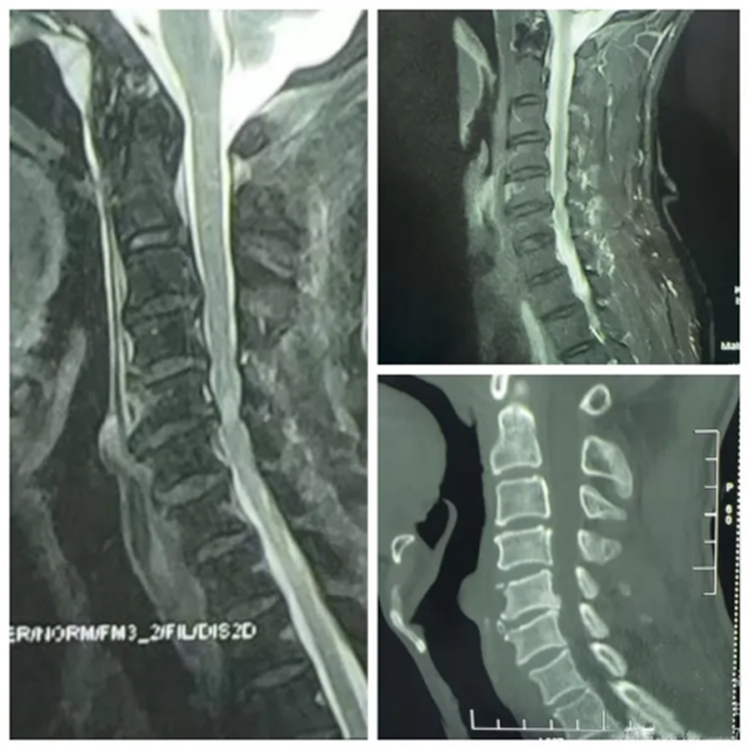

术前影像资料

经亲友推荐,赵大爷来到长沙泰和医院脊柱外科求助。科主任、留日博士宋西正教授详细问诊并阅片后,诊断其为“无骨折脱位型颈脊髓损伤”(亦称“挥鞭样损伤”)。宋教授解释,患者本身存在严重颈椎病,椎管原有狭窄,外伤虽未引起骨折,却导致脊髓内血肿,进一步挤压神经,如同“最后一根稻草”,可能造成永久性神经损伤甚至瘫痪。